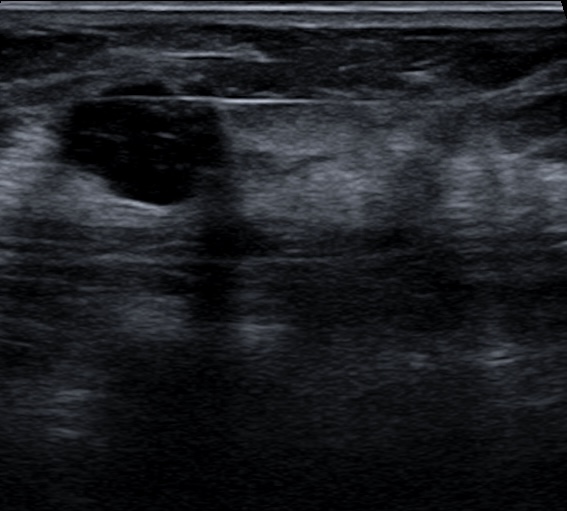

- Masa sólida: Unitaria, circunscrita y no calcificada (ej. probable fibroadenoma).

- Asimetría focal: Visible en dos proyecciones, sin correlato en ultrasonido y no palpable.